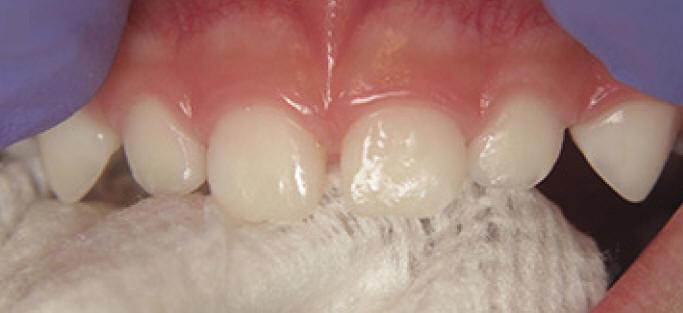

Técnica de aplicación profesional del barniz fluorado (Clinpro White Varnish)

1. Cepillado manual para eliminar placa bacteriana de la superficie dental

2. Ubicar rollos de algodón en el cuadrante que se va a trabajar

3. Secado de los dientes con gasa (figura 1)

4. Aplique una capa delgada de barniz de una sola vez, lo más rápido posible (figura 2) notará que el barniz se vuelve más firme, porque seca muy rápido en ambientes cálidos ó en contacto con los dientes.

Figura 1